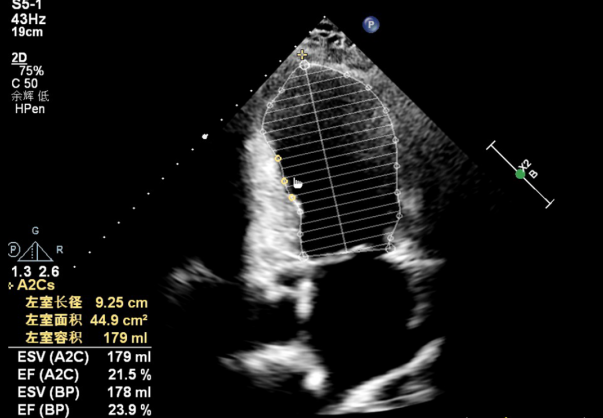

抵达上海后,阿迪力的病情牵动着所有人的心。心功能极差、射血分数不足正常人一半,还合并多种基础病,手术难度极大、风险极高。就在家属濒临绝望之际,万峰院士团队向他们伸出了援手。作为国内心脏外科领域的权威,万峰院士从业40余年,用一双妙手挽救了无数生命,面对阿迪力的病情,他没有丝毫犹豫,主动牵头会诊,安抚家属情绪:“放心,我们一定会尽全力救他。”